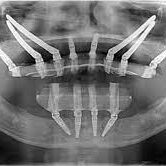

Before and After

SEE OUR RESULTS